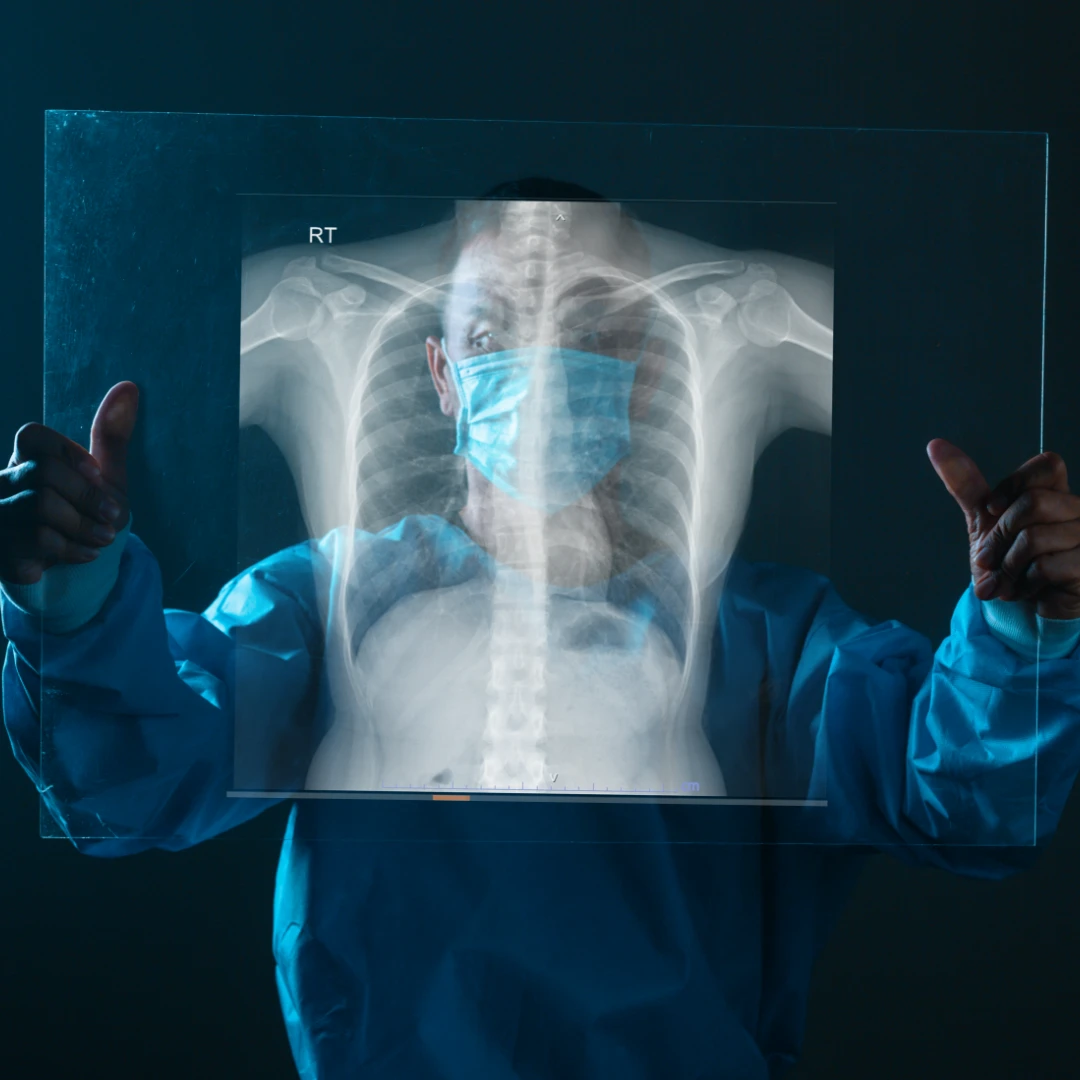

Chest X-ray: useful in evaluating lung abnormalities such as infection and tumour. The surrounding structures, such as the silhouette of the heart and the anatomy of the ribs, can also be seen in a chest X-ray.